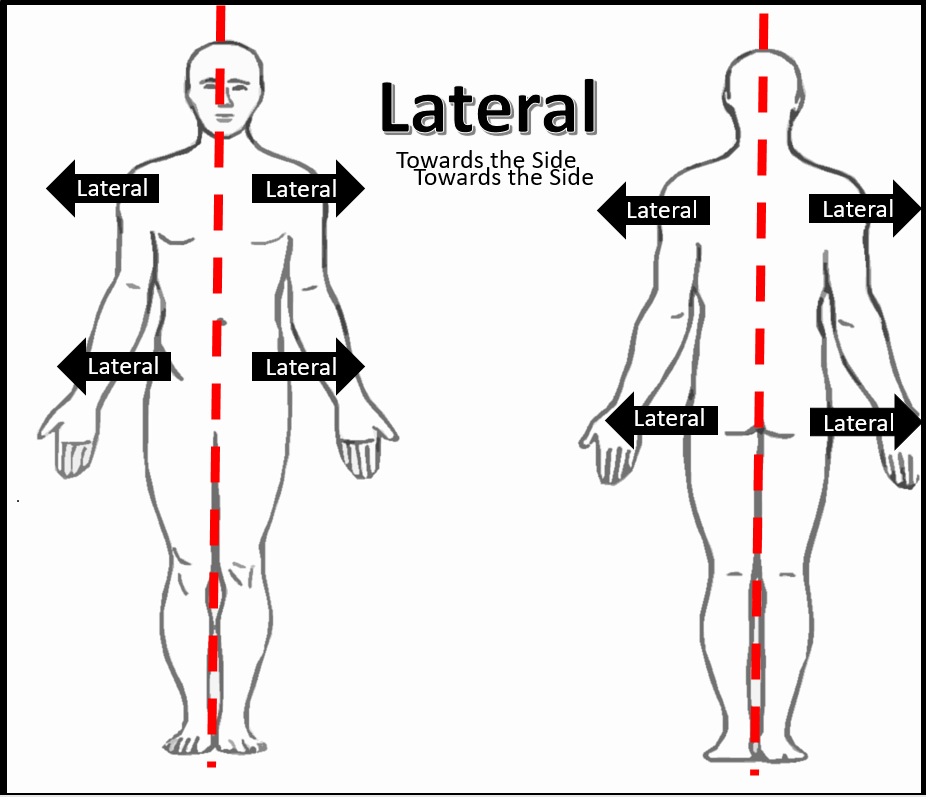

Anatomical Positions – SCIENTIST CINDY